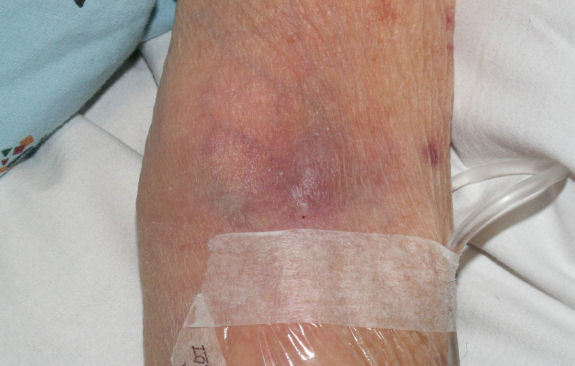

静脉炎临床表现:沿静脉走向出现条索状红线,局部组织出现发红、肿胀、灼热、疼痛,可伴有畏寒、发热等全身症状。美国静脉输液协会(INC)将静脉炎按照严重程度分为五级,为判断静脉炎严重程度的有效标准0级无临床症状1级输液部位发红,伴有或无疼痛2级输液部位疼痛,伴发红和或肿胀3级输液部位疼痛,伴

静脉炎分级标准分级描述0级没有症状1级输液部位发红,伴或不伴疼痛2级输液部位疼痛,伴有发红和/或水肿3级输液部位疼痛,伴有发红和/或水肿,条索状物形成,可触摸到条索状静脉4级输液部位疼痛,伴有发红和/或水肿,可触摸到条索状的静脉> 2.5cm,有脓液渗出

静脉炎在临床上主要分为4级,0级就是没有症状,一级的话输液部位会发红,二级输液部位会疼痛并水肿。三级输液部位会有条索状物形成。4级的时候,这些静脉条索状突起长度会增加并流出脓液。常用的治疗方法有冷敷法,药物湿敷,云南白药湿敷等。